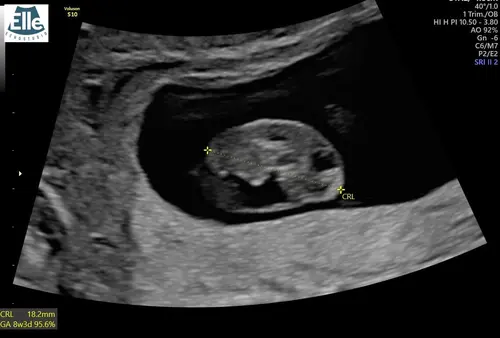

Dit is die van vandaag kreeg 2 dagen later aan gegeven dan eerst nu 6-8 uitgerekend